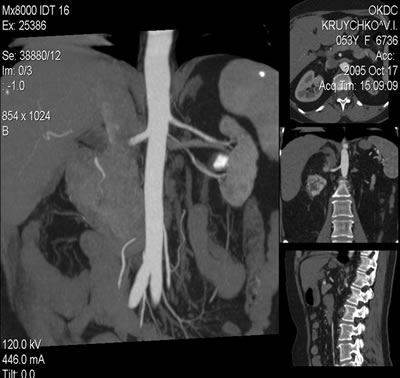

Спиральная компьютерная томография (СКТ) :

Левая почка: размер 70х40 мм, паренхима 12 мм, в ЧЛС - коралловидный конкремент, в нижнем сегменте образование жировой плотности до 6 мм.

Спиральная компьютерная томография (СКТ):

Правая почка: образование 37х41 мм, распространяю-щееся на почечный синус и паранефральную клетчатку.

Спиральная компьютерная томография (СКТ)